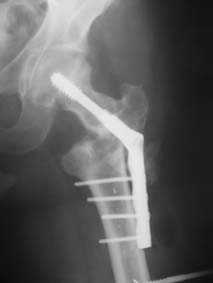

Персонально я бы применил 95-градусную Blade Plate, конструкция которого в головке бедра создаст большую стабильность, чем DHS или другие цефало- медуллярные конструкции. Латеральный внесуставной подвастусный доступ создаст отличное обозрение и костная пластика из крыла таза облегчит сращение.

Я думаю в данном случае для начала необходимо наложить спице - стержневой аппарат таз - бедро с низведением проксимального отломка. Во-вторых открытый остеосинтез DHS c костной аутопластикой. Доступ чрезъягодичный. В даанном случае возможны большие трудности при введения gamma.

95-градусную Blade Plate с костной пластикой уже применял при ложных суставах вертельной области с хорошими результатами. Гамма-гвоздь посчитал как более продвинутую успешную технологию. Согласен, что установка Гамма-гвоздь вызовет трудности. Принимаю вариант с Blade Plate с костной пластикой, это будет более надежно, да и проще технически и материально.

В приложении пример пациента, близкого по картине к тому, что представил Виктор (варус и смещение периферического отломка на поперечник кзади). Сделали как раз то, что Виктор исходно намеревался - аппаратная коррекция и затем гамма.

2. Провести оперативное лечение: закрытый металоостесинтез DHS с костной аутопластикой (максимально восстановив длину конечности на ортопедическом столе). Костный трансплантант взять с диафиза боьшеберцовой кости и ввести его выше винта DHS. В течении 3 мес наступит сращение.

Думаю сделать так: под адекватной анестезией на тракционном столе попробую максимально низвести бедро. Если получится, рентгенконтроль/оценка ситуации и Blade Plate с костной пластикой (помню предостережение Александра Николаевича о возможной варусно-антекурвационной установке центрального отломка и трудности в использовании Гамма-гвоздя). Если останется укорочение на 3-4 см придется на короткое время (2-2,5 недели) наложить стержневой аппарат "бедро-бедро" и дробно, но форсированно, ориентируясь на ощущения больного и поведение дистальных отделов конечности адаптировать отломки (больной на это период останется в стационаре). Если же появятся первые признаки воспаления мягких тканей в области проксимальных стержней, аппарат снимаю, перевожу на скелетное вытяжение и готовлю больного ко второму этапу.